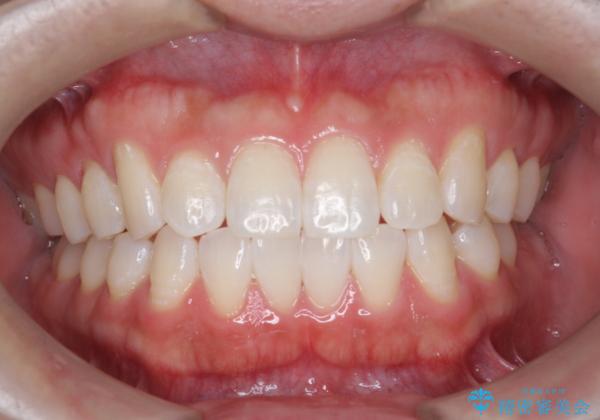

オフィスホワイトニングで、歯を白く!

オフィスホワイトニング(エクセレント)

医院で行う、オフィスホワイトニングで歯が白くなり、喜んでいただけました。